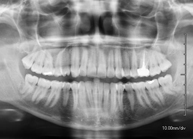

Técnica mediante la cual, utilizando rayos X, se obtienen imágenes de los senos paranasales para su estudio. Indicaciones: dificultad respiratoria nasal, tos crónica, cefalea, mucosidad. - RX ATM (Articulación Temporo-Mandibular)

Técnica mediante la cual, utilizando rayos X, se obtienen imágenes de la articulación temporo-mandibular para su estudio. Indicaciones: traumatismo, dolor al masticar, ruido al masticar, limitación en la apertura bucal. - RX Cavum

Técnica mediante la cual, utilizando rayos X, se obtienen imágenes de la mandíbula para su estudio. Indicaciones: traumatismo, anomalías congénitas. - RX Laringe